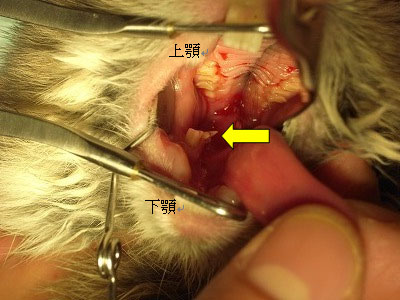

口腔内の様子。

下顎臼歯にスパイク(突起)を形成している。

出血も認める。

上顎臼歯にも軽度にスパイクを形成している。